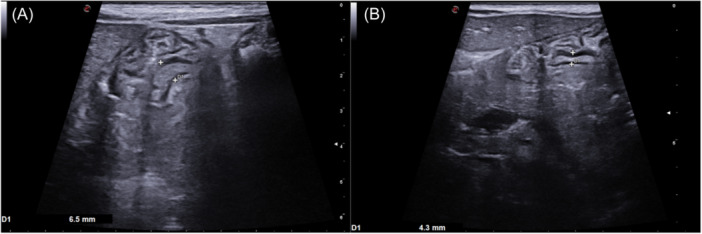

Menetrier's disease (MD) is a protein-losing gastropathy characterized by acute generalized edema due to hypoalbuminemia. MD is rare in childhood, and it is commonly associated with cytomegalovirus infection. We reported two children, who presented with a history of generalized edema after some days of abdominal pain and diarrhea. Laboratory tests showed hypoalbuminemia with no proteinuria. Thoracic and abdominal ultrasound (US) revealed respectively pleural and pericardial effusion and ascites. A specific gastric echography showed gastric wall thickening (>3 mm) and upper gastrointestinal endoscopy revealed prominent folds in the gastric body and fundus, with a subsequent histological confirmation of Menetrier diagnosis. They were discharged after several albumin infusions. A US follow-up confirmed the remission of the disease after 1 and 6 months. Gastric US revealed accurate in the diagnosis of this rare condition and in its follow-up. avoiding a second endoscopy in the short term.